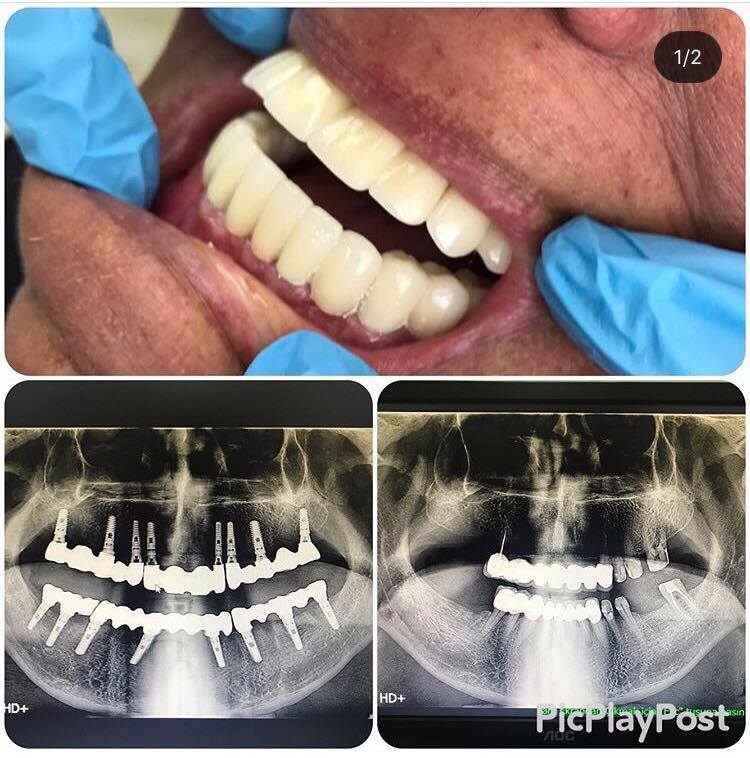

İMPLANT TEDAVİSİ

implant tedavisi